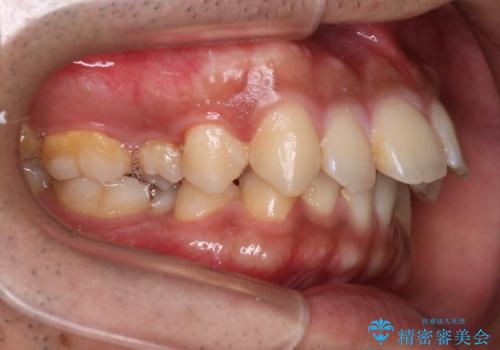

- 歯並びの凸凹を主訴に来院されました。

スペースが必要なため、抜歯を行なって治療を行いました。

奥歯の捻れが強く治療期間がかかりましたが、綺麗な仕上がりに満足していただきました。